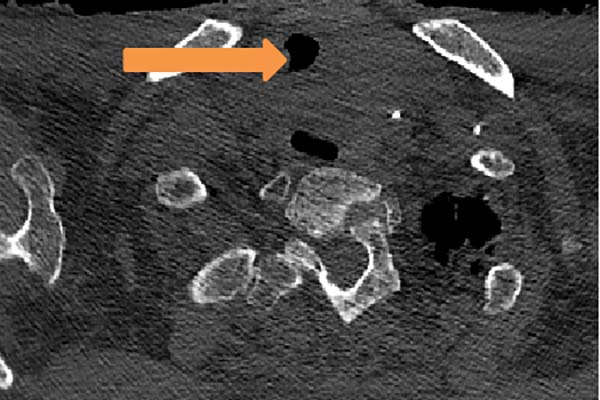

图1术后CT(箭头处为原气道最狭窄处)